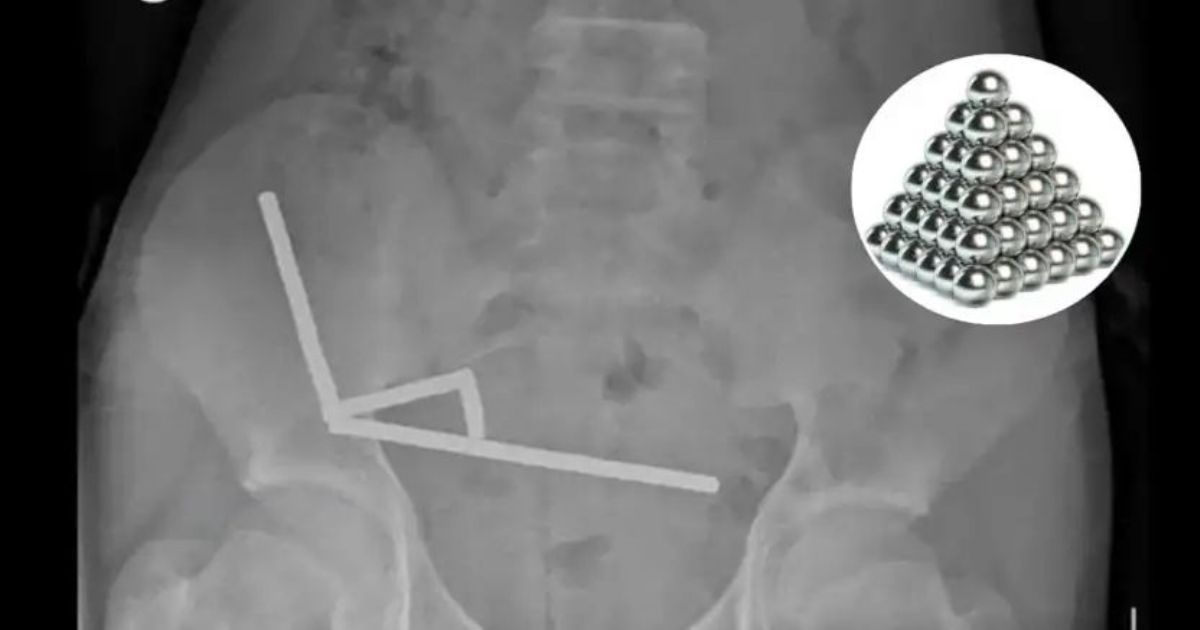

நியூசிலாந்தில் 13 வயது சிறுவன், ஆன்லைன் தளத்தின் மூலம் அதிக சக்தி வாய்ந்த காந்தங்களை வாங்கி, அவற்றைப் பலமுறை விழுங்கியதால் தீவிர சுகபாதை ஏற்பட்டது. வயிற்று வலியால் துன்பப்பட்ட அந்த சிறுவன் மருத்துவமனைக்கு கொண்டு செல்லப்பட்டு அவசர அறுவை சிகிச்சைக்கு உட்படுத்தப்பட்டான்.

சுமார் 80 முதல் 100 சிறிய காந்தங்கள் அவனது குடலில் ஒட்டிக்கொண்டதை மருத்துவர்கள் கண்டறிந்தனர். அவற்றை முழுமையாக அகற்ற முடியாத நிலை காணப்பட்டதால், குடலின் ஒரு பகுதியை அகற்றும் நிலை ஏற்பட்டது என்று டௌரங்கா மருத்துவமனை நிபுணர்கள் தெரிவித்தனர்.

A 13-year-old boy in New Zealand swallowed up to 100 high-power magnets he bought on Temu, forcing surgeons to remove tissue from his intestines, doctors said on Friday.